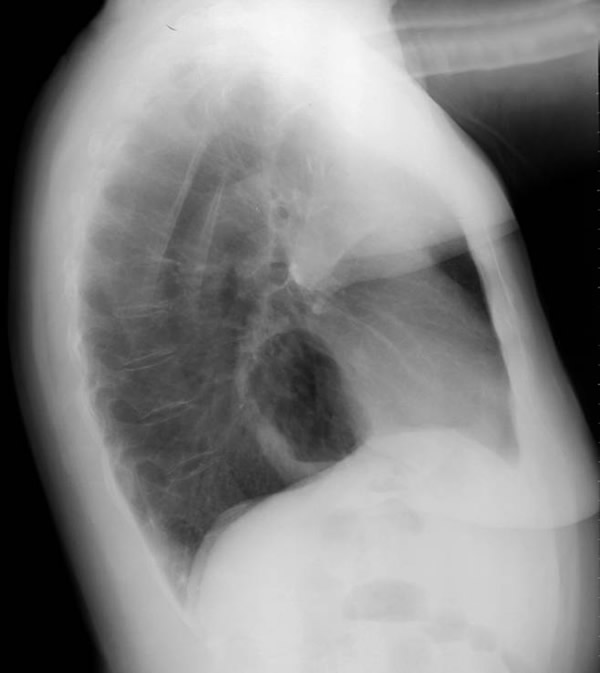

The clinical manifestations are unpredictable and are not influenced by the size of the diverticulum but rather correlate with the underlying motility disturbance. Dysphagia and regurgitation are the predominant symptoms observed. Respiratory complaints, when present, indicate aspiration. Most esophageal diverticuli are found incidentally. Chest radiography may be normal or may reveal a mediastinal density or air-fluid level (Figure 1). This feature may be misdiagnosed as a hiatus hernia. The diagnosis of an epiphrenic diverticulum is usually made on an upper gastrointestinal series (Figure 2). Oblique views can define the size, location, number and shape of diverticula. Contrast studies, however, are unreliable for evaluating motility patterns and thus esophageal manometry should be performed preoperatively. Correct placement of the catheter can be difficult and may be assisted with endoscopic guidance. Esophageal endoscopy is recommended to exclude other etiologies for dysphagia. This maneuver can be difficult and should be performed by an experienced endoscopist.